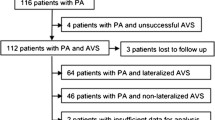

We retrospectively analyzed 154 patients diagnosed with PA and who underwent AVS at our hospital between January 2010 and June 2021. Based on machine learning, we determined predictors of PA subtypes diagnosis from the results of blood and loading tests.

The accuracy of the machine learning was 88% and the top predictors of the UPA were plasma aldosterone concentration after the saline infusion test, aldosterone to renin ratio after the captopril challenge test, serum potassium and aldosterone-to-renin ratio. By using these factors, the accuracy, sensitivity, specificity and the area under the curve (AUC) were 91%, 70%, 99% and 0.91, respectively. Furthermore, we examined the surgical outcomes of UPA and found that the group diagnosed as unilateral by the predictors showed improvement in clinical findings, while the group diagnosed as bilateral by the predictors showed no improvement.